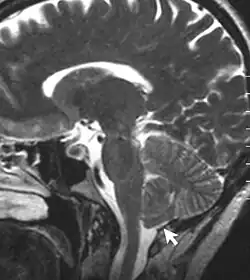

Chronic secondary headache or orofacial pain is a result of an underlying disorder.[24] Chronic secondary headache or orofacial pain can be caused by ischemic stroke, nontraumatic intracranial hemorrhage, arteritis, unruptured vascular malformation, pituitary apoplexy, genetic vasculopathy, increased cerebrospinal fluid pressure, Chiari malformation type I, intracranial neoplasms, epileptic seizure, substance withdrawal,[24] bacterial meningitis, meningoencephalitis, viral meningitis or encephalitis, brain abscess, intracranial fungal or other parasitic infections, hypoxia, hypercapnia, dialysis, arterial hypertension, and hypothyroidism.[25]